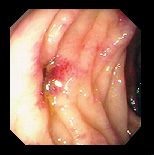

Ce que l'on observe lors d'une coloscopie

![]() |

|

Des diverticules

Une diverticulite

Cancer du Colon